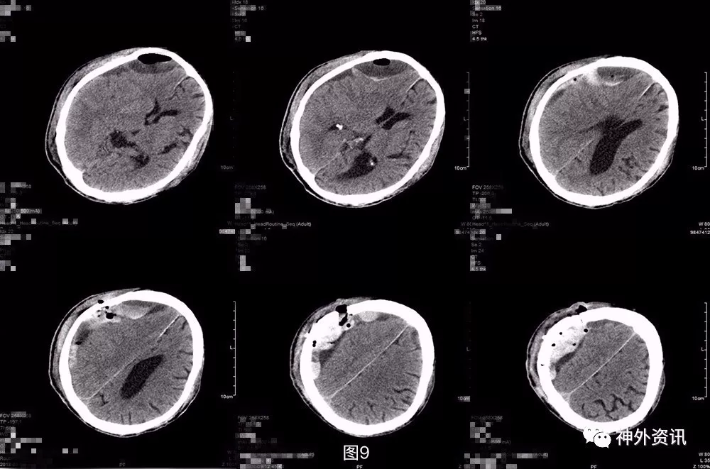

图8. 第三次术后第3天头颅CT提示:局部积血积气积液较前片似有增多。 第三次术后第5天再次复查头颅CT,显示局部积气比前片吸收,但积血积液仍较明显(图9)。考虑患者神志及肢体肌力基本同前,继续予以药物保守治疗。之后患者逐渐神志转清,左侧肢体肌力好转至3-4级,期间复查头颅CT(图10)提示局部积血密度逐渐下降,提示血肿液化可能,于术后半月稳定后转康复治疗,定期复查头颅CT。

图9. 第三次术后第5天头颅CT,显示局部积气比前片吸收,但积血积液仍较明显。

图10. 第三次术后第10天,局部积血密度逐渐下降,提示血肿液化可能。 出院后患者分别于术后3周,术后5周复查头颅CT,提示血肿密度较前持续下降,中线偏移好转,占位效应较前有所缓解(图11)。